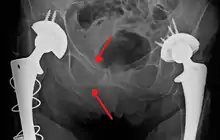

كسر (الكتاب المفتوح )

أحد الانواع الخاصة بكسر الحوض يسمى كسر ( الكتاب المفتوح ) ، عادة تنتج من تأثير ثقيل على المغبن (اصل الفخذ ) على جانبي العانة، مألوفة في إصابات حوادث الدراجات النارية، في هذا النوع من الاصابات، النصفيين الأيمن والايسر للحوض مفصولين عند الامام والخلف، الفتحة الامامية أكثر من الخلفية، مثل الكتاب المفتوح الذي يسقط على الارض ويقسم في الوسط، بالاعتماد على الشدة، ربما يتطلب عملية اعادة تصحيح جراحية قبل اعادة التأهيل.[8] القوى من الاتجاه الامامي أو الخلفي، مثل حوادث السيارات وجهاً لوجه، قد تسبب دوران خارجي لنصفي الحوض، اصابات الكتاب المفتوح . الكسور المفتوحة تزيد خطورة العدوى والنزيف من اصابات الاوعية الدموية تؤدي إلى ارتفاع معدل الوفيات.[9]

الجراحة ، عادة الجراحة مطلوبة لكسور الحوض، الكثير من اساليب تثبيت الحوض تستخدم وتتضمن التثبيت الخارجي ، والتثبيت الداخلي، والجر .[11][12] عادة هناك اصابات اخرى تصاحب كسور الحوض لذلك نوع الجراحة يجب ان يخطط له بدقة.[13]